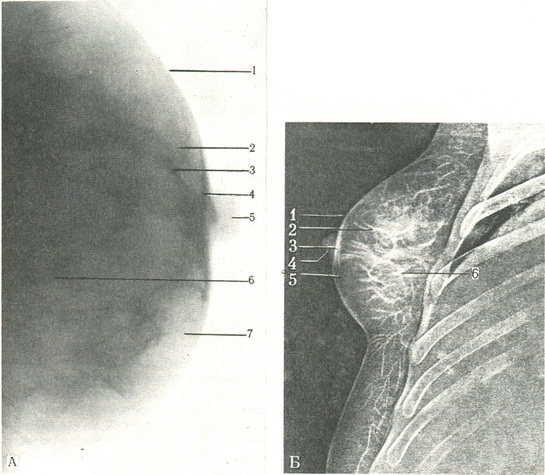

Знімки виконуються в прямій або бічній проекції. На знімках видно тінь шкіри, соска, залозиста тканина, жирова клітковина і кровоносні судини (рис. 544А). Особливо чітко ці структури видно на электрорентгенограммах (рис. 544Б).

544. Рентгенограма (А) і электронограмма (Б) нормальної молочної залози в бічній проекції.

А: 1 - шкіра; 2,7 - підшкірна клітковина; 3 - вена; 4 - поле соска; 5 - сосок; 6 - тіло залози. Б: 1 - cutis; 2 - venae; 3 - areola mammae; 4 - papilla mammae; 5 - tela subcutanea; 6 - corpus mammae.